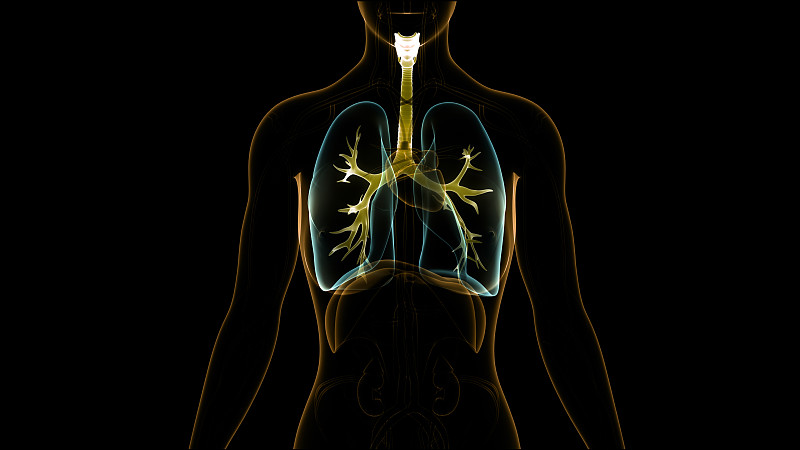

人体呼吸系统解剖学详情

JPG